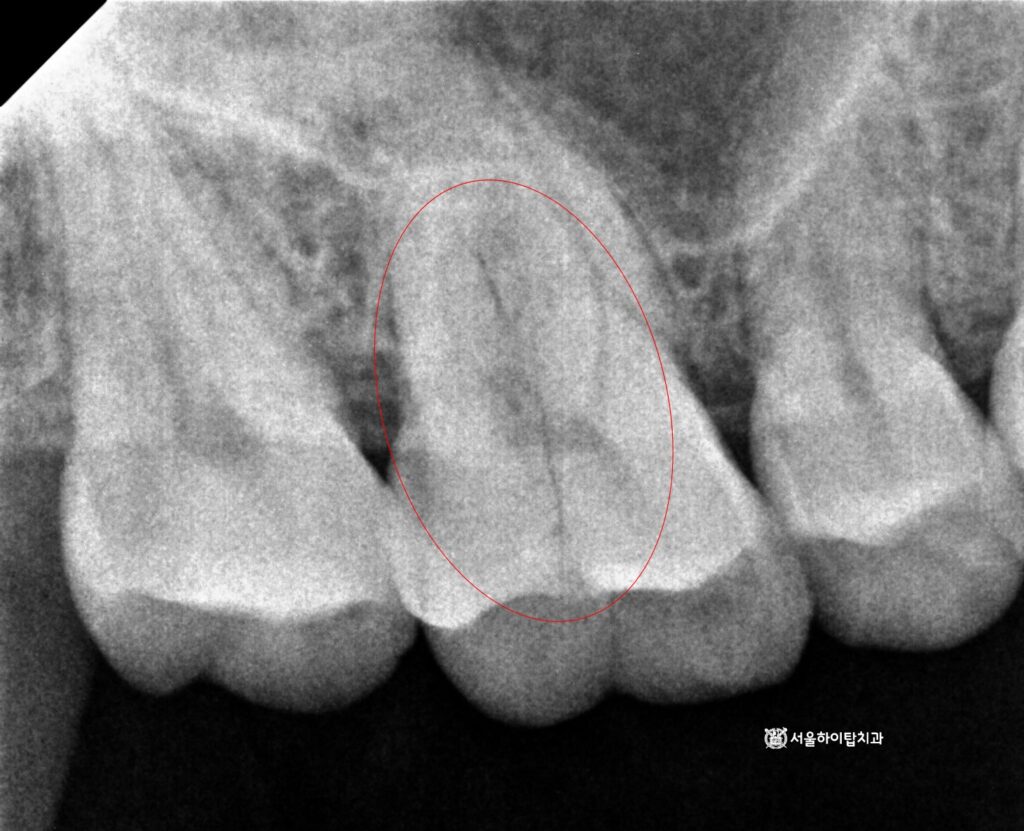

이어서 반대편으로 넘어가면,

치관부 중앙에서 치근단까지 이어지는

명확한 파절선(fracture line)이 관찰됩니다.

이는 단순 균열을 넘어

치근 파절(root fracture) 로

진행된 상태로 볼 수 있습니다.

현재 양쪽 모두에서

문제가 발생한 상황이므로,

정밀한 진단과 치료 계획 수립을 위해

CT 촬영이 필요합니다.